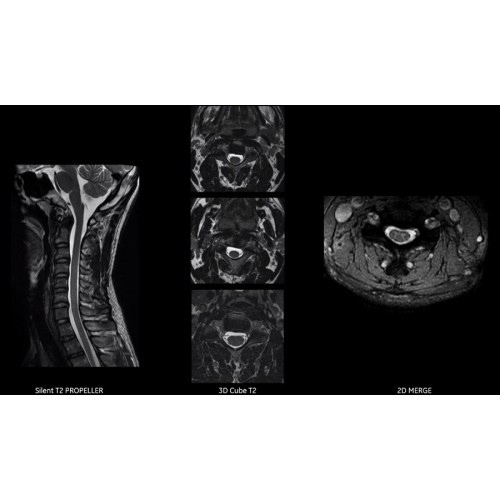

МРТ аппарат GE SIGNA Voyager 1.5T позволяет проводить полный спектр магнитно-резонансных исследований, включая нейровизуализацию, исследования опорно-двигательного аппарата, органов брюшной полости и малого таза, а также специализированные кардиологические программы.